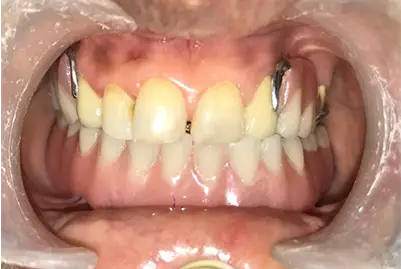

Post TreatmentCase 2: Maxillary cast partial denture & Mandibular

Tooth supported overdenture - ceka

attachment